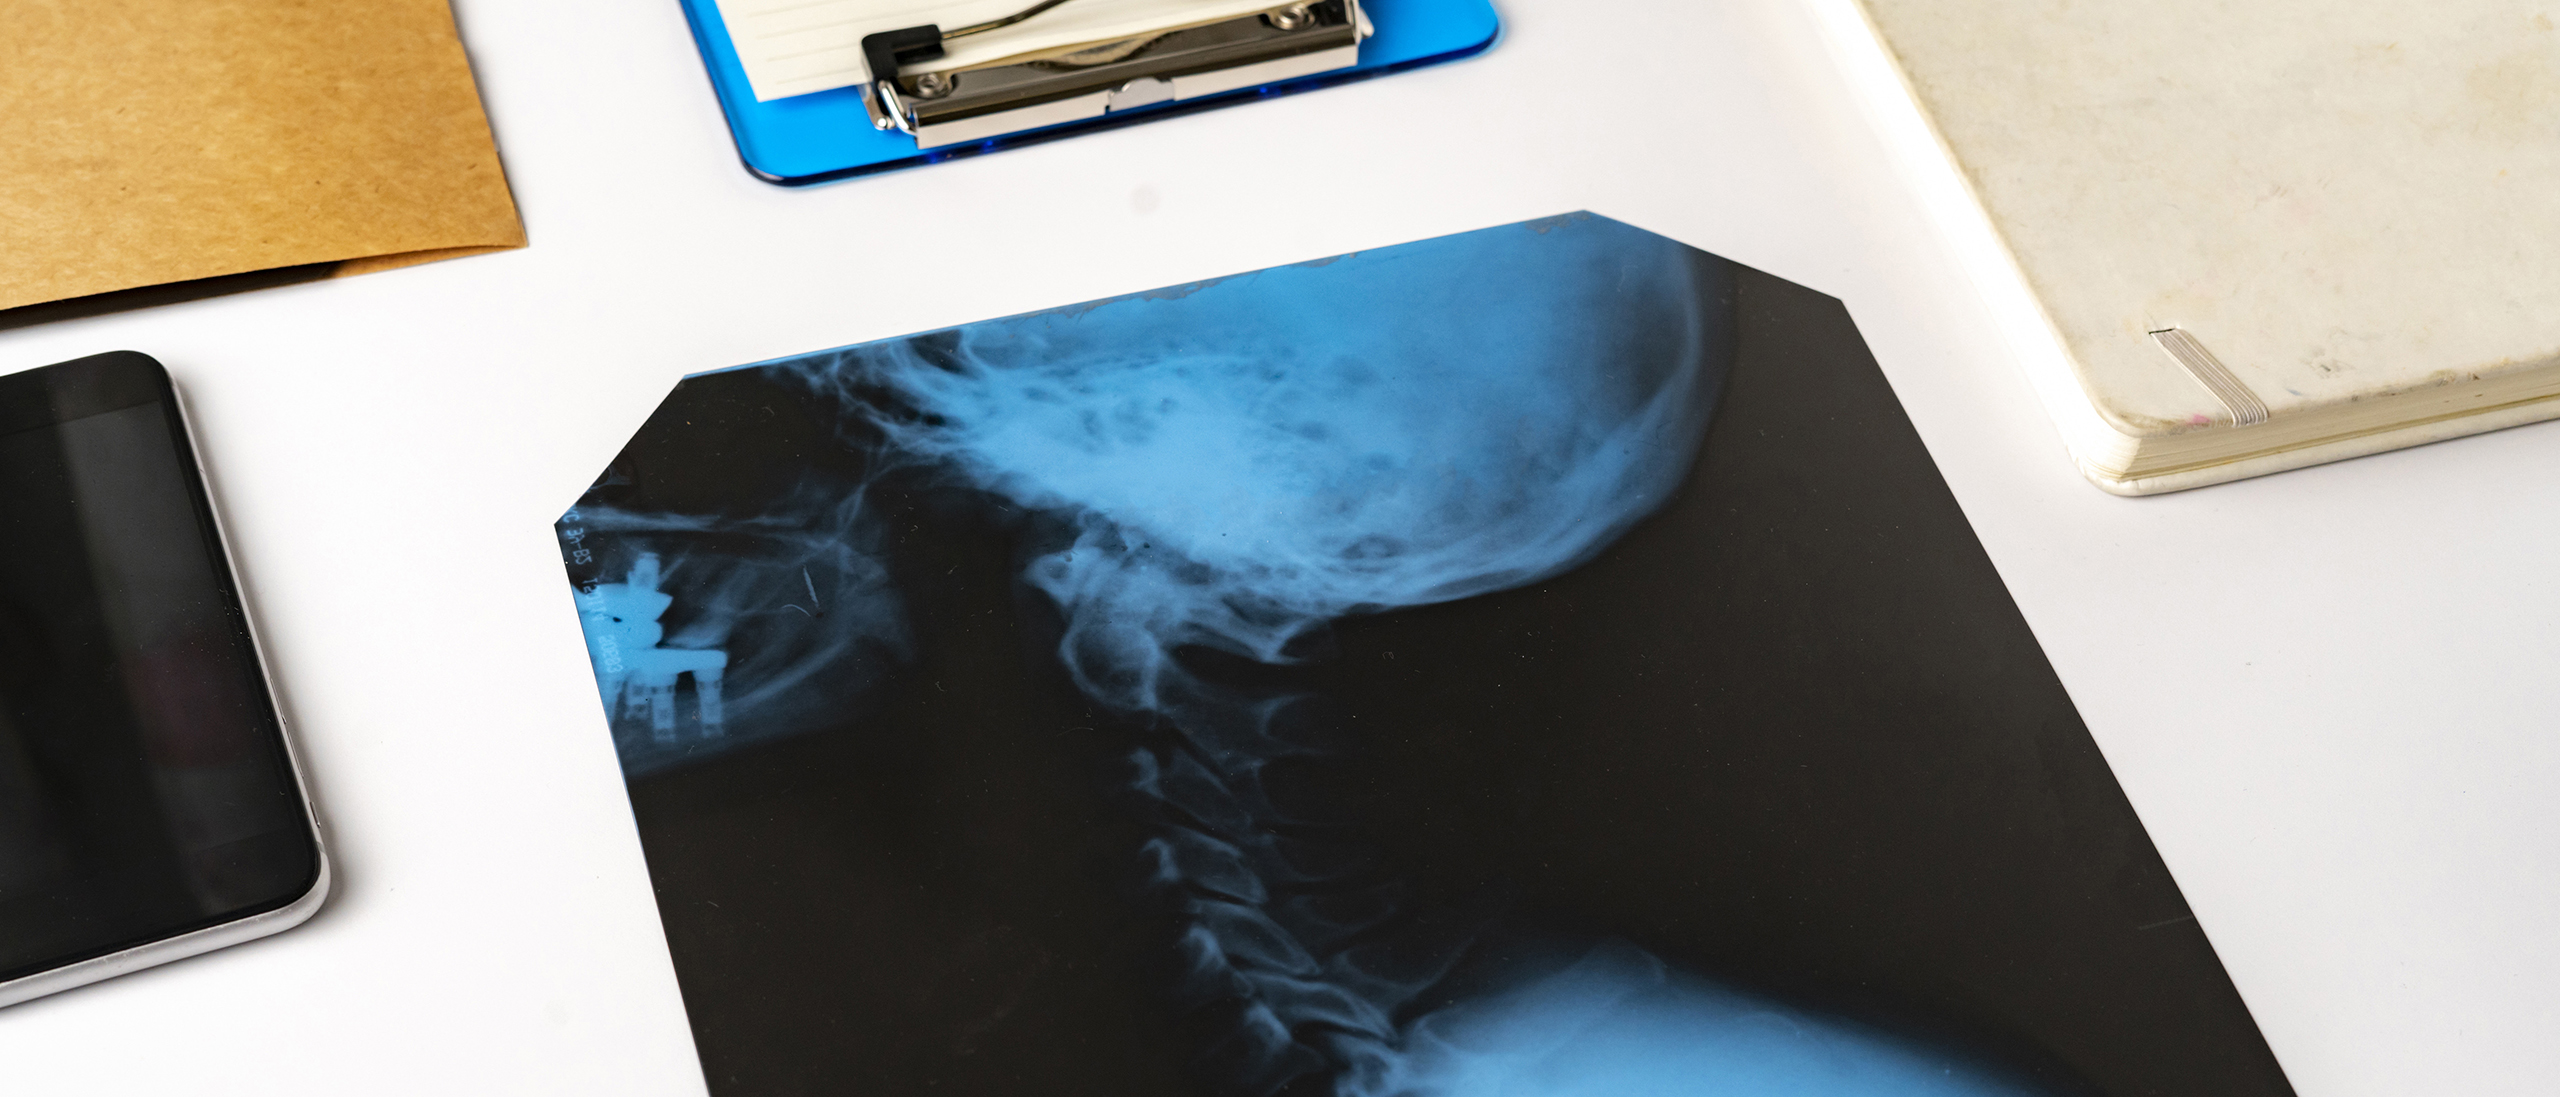

Radiologia ed Ecografia

Diagnosi precise, rapide e sicure grazie a tecnologie di ultima generazione e specialisti dedicati

Presso Medical Clinique offriamo un servizio di diagnostica per immagini completo e di alta qualità, grazie a tecnologie digitali di ultima generazione e a un’équipe di specialisti dedicati.

Il nostro Polo Radiologico integra radiologia tradizionale ed ecografia, per garantire diagnosi rapide, accurate e non invasive, fondamentali per la prevenzione e il monitoraggio di numerose patologie.

• Radiologia Tradizionale: Utilizziamo apparecchi digitali avanzati che riducono al minimo l’esposizione ai raggi X per pazienti e operatori.